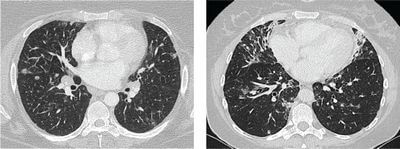

КТ стали важливим інструментом моніторингу ефективності лікування захворювань. КТ може допомогти медичним працівникам визначити, чи працює лікування, візуалізуючи зміни у внутрішніх структурах організму. Наприклад, якщо пацієнт проходить хіміотерапію для лікування раку, КТ можна використовувати для моніторингу розміру пухлини. Якщо пухлина зменшується, це означає, що лікування працює.

КТ-сканування використовують для оцінки лікування захворювань у різних медичних станах. Деякі з найпоширеніших захворювань, при яких використовується КТ, включають рак, серцево-судинні захворювання та неврологічні розлади. КТ може допомогти медичним працівникам визначити ефективність хіміотерапії або променевої терапії для лікування раку. Вони також можуть використовуватися для моніторингу прогресування серцево-судинних захворювань або ефективності лікування неврологічних розладів.